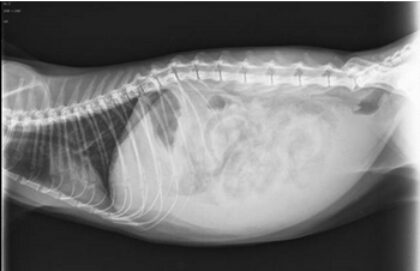

Thoraxergüsse und Aszites werden bei Kleintieren häufig beobachtet und nicht ausreichend diagnostisch ausgewertet.

In diesem vetinar wird die systematische diagnostische Aufarbeitung von Thoraxergüssen und Aszites erläutert. Dabei werden die zugrundeliegenden pathophysiologischen Mechanismen und die Vielfalt möglicher Grunderkrankungen diskutiert. Anhand von Fallbeispielen werden die verschiedenen Ursachen und die möglichen therapeutischen Ansätze beschrieben. Dabei werden klinische Daten, Blutergebnisse, Bildgebungsbefunde und zytologische Bilder zahlreicher Patienten analysiert.